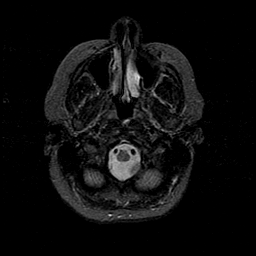

MR Study #1 -- Slice #8

[Home][Help][Clinical][Tour 1][Tour 2][Tour 3] Slice 8